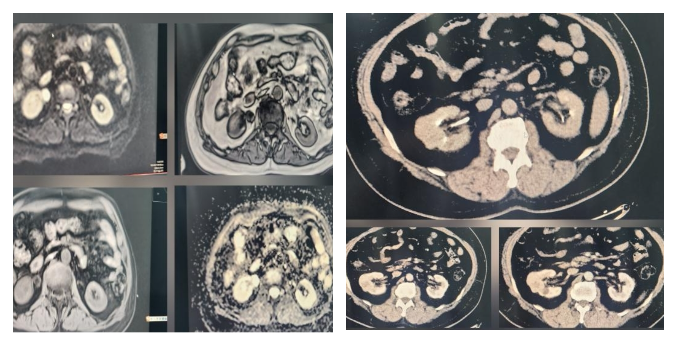

此次接受手术的两位患者均被确诊为泌尿系统恶性肿瘤,其中一名为蒙古国患者,曾辗转多处就诊。两名患者病情复杂,手术难度大,其中一台腹腔镜下肾癌根治术要求精准、完整地切除患肾及周围组织,避免肿瘤扩散;另一台腹腔镜下输尿管癌根治术则需切除范围更广,包括肾脏、同侧全长输尿管及部分膀胱,是泌尿外科领域公认的高难度手术之一。

手术一:腹腔镜下输尿管癌根治术——手术范围虽大,但过程流畅,完整切除了病变的肾脏、输尿管及部分膀胱,术中给予抗肿瘤药物膀胱灌注,避免肿瘤种植,实现了肿瘤的根治性切除。

手术二:腹腔镜下肾癌根治术——团队接力进行,清晰解剖肾脏周围结构,精准分离、结扎血管,完整切除肿瘤,将手术创伤和出血量降至最低。